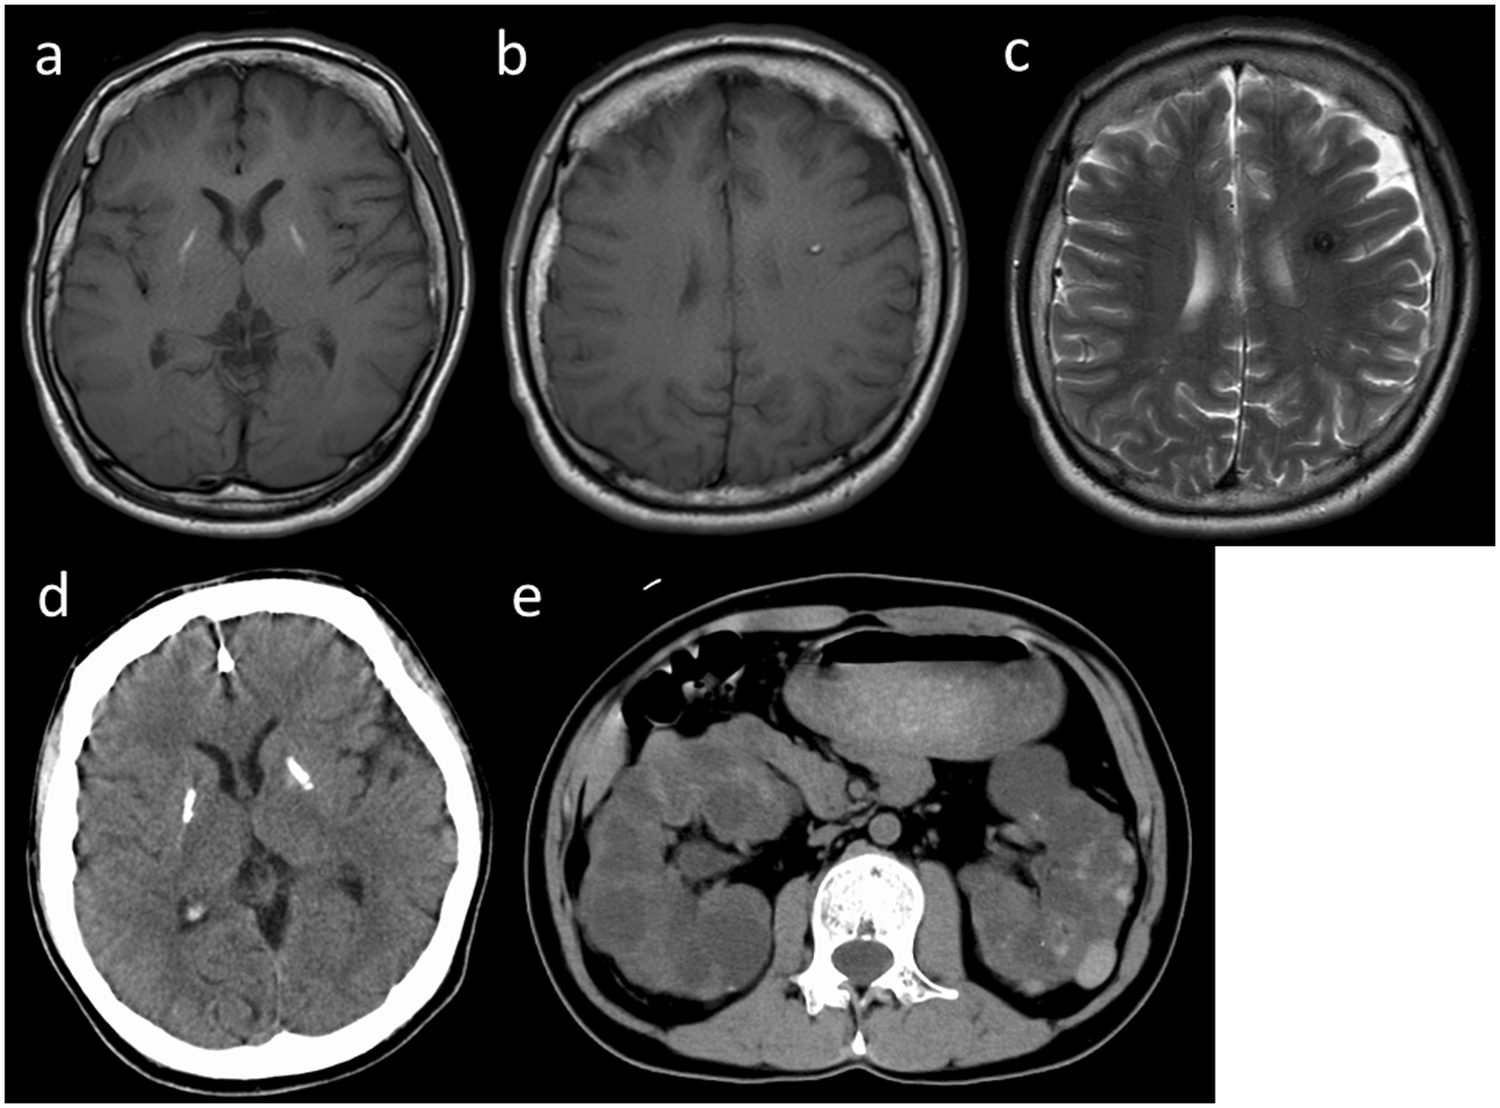

Fig. 1: Imaging results of the patient.

Brain magnetic resonance imaging (MRI) and head computed tomography (CT) were performed when the patient was 32 years old. a, b T1 weighted imaging (T1WI), c T2WI, d head CT, and e abdominal MRI.